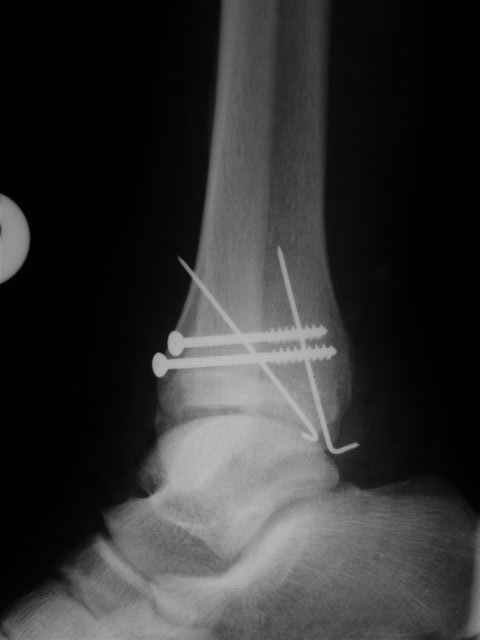

Уважаемый Иван,

Я предупреждал, что ничего сверхъестественного. Каюсь, что одна из спиц прошла несколько дальше, чем нужно было, но главное - перелом стабилизирован и больной работает суставом в полном объёме, несмотря на представленную раннее травму коленного сустава.

Всего вам Доброго,

Евгений И Чекашкин